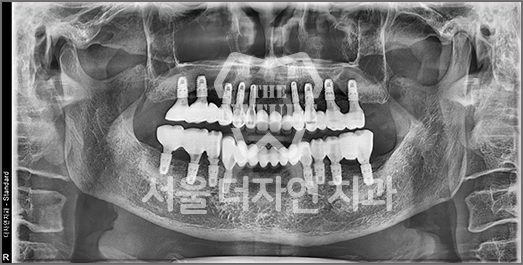

Implant Revision Surgery

Revision implant surgery is more challenging

and complex than the original procedure

Improper implant surgery or inadequate implant maintenance can lead to complications accompanied by pain. Implant revision surgery involves removing the existing implant, rebuilding the alveolar bone, reshaping the gingival contour,

and placing a new implant in the correct position.

• BEFORE: 2021.11.02

• AFTER: 2022.01.19

An implant placed at another clinic was found to be significantly mispositioned,

requiring revision surgery to correct the placement to the proper position.